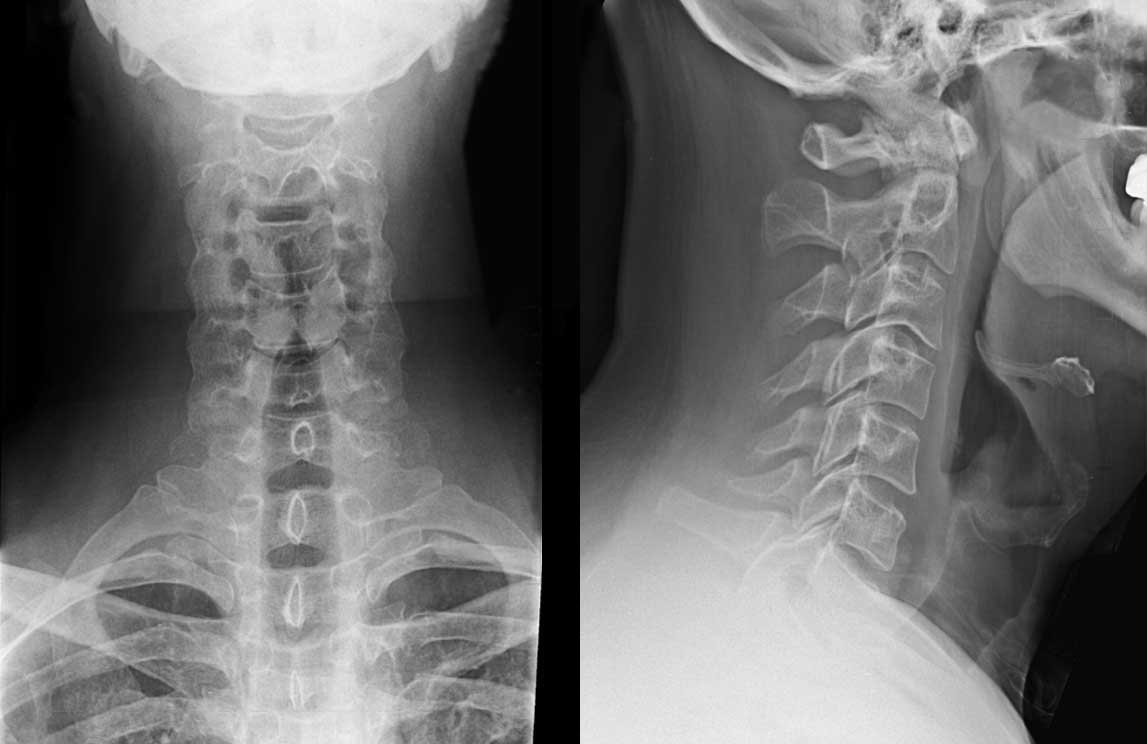

Đặc điểm cấu tạo 7 đốt sống cổ

7 đốt sống cổ có một số đặc điểm như sau: Đầu tiên, cuống tách ra từ phần sau của mặt bên thân đốt sống cổ và khuyết sống trên-dưới đều có độ sâu ngang bằng nhau. Các đốt mảnh, hình vuông, chiều rộng lớn hơn chiều cao, đỉnh của mỏm gai tách làm hai củ. Mỏm ngang thì dính vào thân và cuống qua 2 rễ giới hạn và có một lỗ được gọi là lỗ ngang để cho mạch đốt sống chui ngang qua. Đỉnh của mỏm ngang tách ra thành củ trước đốt sống cổ và củ sau đốt sống cổ còn mặt trên của mỏm ngang có rãnh thần kinh gai sống. Bên cạnh mỏm ngang, có một bộ phận gọi là mỏm khớp có diện khớp phẳng nằm ngang. Trong đó, diện trên nhìn lên trên và ra sau còn diện dưới nhìn xuống dưới và ra trước. Lỗ của đốt sống cổ có hình tam giác và rộng hơn ở các lỗ đốt sống ngực hay thắt lưng để thực hiện chức năng chứa đoạn phình cổ của tủy gai và thích ứng với biên độ di động lớn của đoạn sống cổ. Đặc biệt, nếu hỏi về đặc trưng quan trọng nhất để xác định một đốt sống cổ thì đó chính là lỗ ngang.

Giải phẫu đặc điểm 7 đốt sống cổ

Đốt sống cổ 1 (Đốt sống đội)

Đốt này không có thân sống nên hình dạng giống như một cái vòng với hai khối bên có hố khớp trên để khớp với đốt sống cổ 2. Nhờ vào cung trước ở phía trước và cung sau ở phía sau, hai khối bên sẽ được nối nhau. Phía trước cung sẽ lồi ra một khoảng ở thành củ trước và phía sau lại lõm vào để tạo thành hố răng giúp đốt sống cổ 1 khớp với răng của đốt cổ 2. Ở phía sau của đốt sống này lồi ra và tạo thành củ sau, phía trên sát với khối bên sẽ có rãnh động mạch đốt sống.

Đốt sống cổ 2 (còn được gọi là đốt sống trục)

Đốt sống cổ 2 là đốt dày và khỏe nhất trong các đốt sống cổ. Đốt có một mỏm mọc lên trên thân được gọi là “răng”. Mỏm răng có hình tháp và cao 1,5cm được coi như thân của đốt đội dính vào đốt trục để làm trục cho đốt đội quay. Ở phía trước răng, đốt sống cổ 2 có diện khớp trước để khớp với hố răng của đốt đội (đốt sống số 1) và có một diện khớp sau để khớp với dây chằng ngang của đốt đội.

Đốt sống cổ 4

Đốt sống này có đặc điểm là mỏm ngang lồi to ra thành củ cảnh. Củ này nếu như to quá có thể chèn vào động mạch cảnh chung. Đây cũng là mốc gặp gỡ của động mạch cảnh chung với động mạch giáp dưới và động mạch đốt sống.

Đốt sống cổ 7

Đốt sống cổ số 7 có đặc điểm là mỏm gai không chẻ đôi và dài hẳn ra, khi sờ vào sẽ có thể nhận biết được dưới da nên còn có thể được gọi là đốt sống lồi. Lỗ ngang của đốt này rất nhỏ, có khi không có. Đốt sống cổ 7 nằm ở ranh giới giữa đoạn sống cổ và đoạn sống ngực nên có nhiều đặc điểm chuyển tiếp giữa đốt sống cổ và đốt sống ngực.